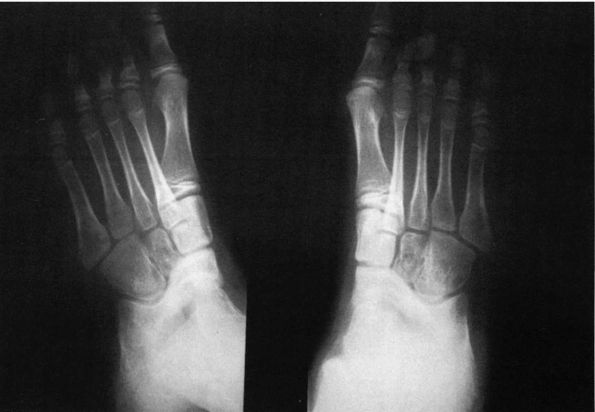

|

FIGURE 20-17. A talocalcaneal bridge. Harris views of both feet. Note the prominence of the sustentaculum (arrow A); talocalcaneal articulation is obliterated in the medial portion (arrow B).